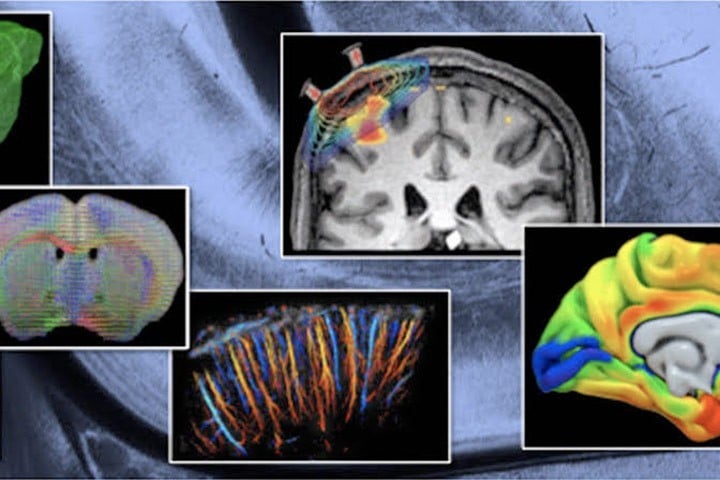

About the course